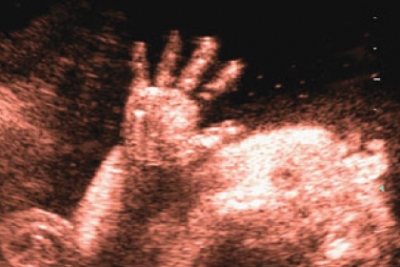

Quella eseguita tra 19 e 21 settimane gestazionali, la famosa, agognata e temuta ecografia morfologica il cui scopo principale, celato spesso dalla curiosità di conoscere il sesso del nascituro, è in realtà accertarsi del corretto sviluppo dei suoi organi vitali, verificare la placentazione e valutare il liquido amniotico.

E infine l’ecografia delle 32 settimane di gestazione conosciuta anche come ecografia di accrescimento perché una delle sue funzioni principali è quella di valutare la crescita del feto, oltre che ovviamente controllare il suo benessere, placentazione e liquido amniotico.